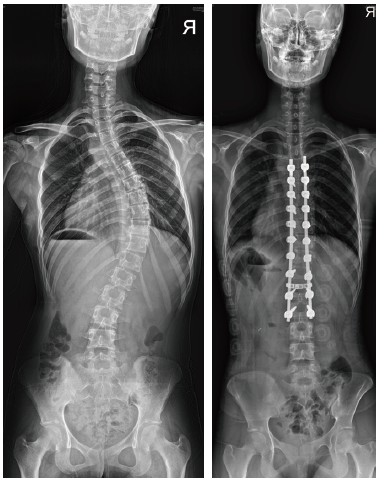

- 성장이 많이 남은 어린 아동에서 측만증이 심할 경우 그림과 같이 만곡의 위아래에만 일시적 고정 후 성장할 때 마다 강봉을 늘려 성장이 종료될 때까지 만곡의 진행을 방지합니다.

- 성장이 끝난 경우에는 교정이 필요한 모든 척추체에 고정을 하고 강봉을 이용하여 만곡을 교정하고 교정 후에는 골유합을 시행하게 됩니다.

- 허리쪽의 만곡이 심한 경우는 요추의 어느 부분까지 고정 할지가 중요합니다. 고정 범위가 길어지면 교정은 좋아 지지만 움직일 수 있는 허리의 운동 범위가 줄어듭니다. 보통 생활에는 지장이 없지만 허리의 운동 범위를 보존해 주는 것이 좋기 때문에 수술이 필요한 경우에는 만곡이 뻣뻣해 지기 전 적절한 어린 나이에 고정을 해주어 수술 범위를 필요한 부분만 하는 것이 좋습니다.